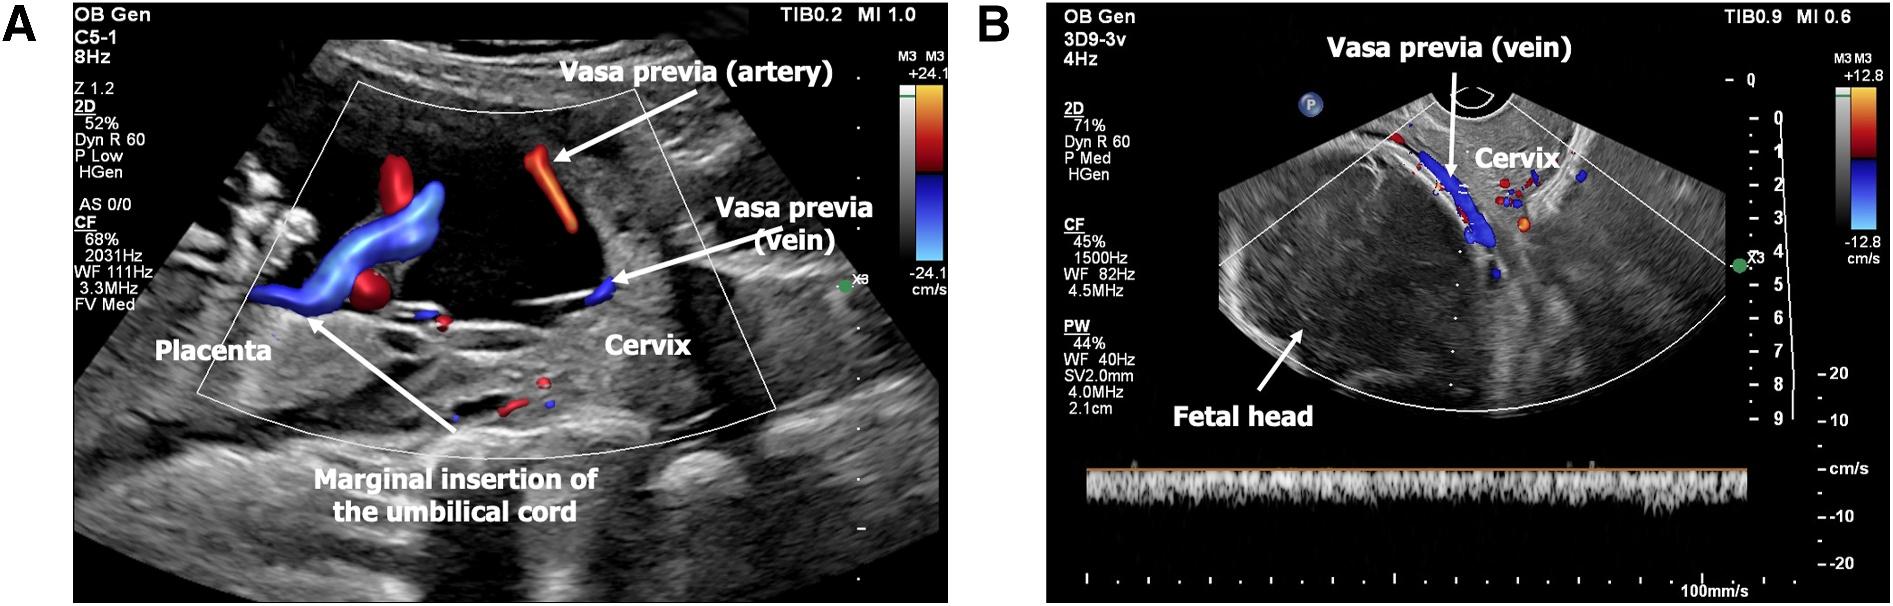

A 40‐year‐old woman, gravida 3, abortus 2, was referred to our fetal therapy center at 22 weeks and 5 days of gestation due to advanced maternal age and a suspected diagnosis of vasa previa identified on routine obstetric ultrasound. Serial follow‐up ultrasounds confirmed a low‐lying posterior placenta with marginal cord insertion, along with an anterior succenturiate placental lobe. Color Doppler imaging demonstrated a vasa previa composed of one vein and one artery crossing the internal cervical os, consistent with Type II vasa previa (Figure 2A,B).